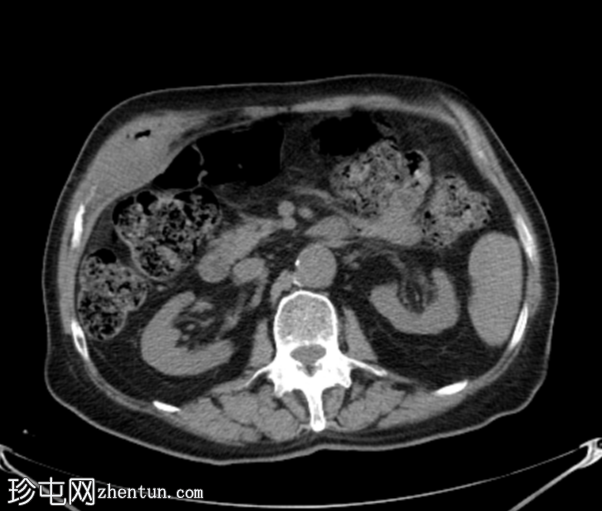

轴位

平扫

胆囊底部可见一枚较大的(3厘米)高密度结石,胆囊壁增厚并强化,主要位于胆囊底部。胆囊壁可见一小穿孔,感染扩散至胆囊外,并在肝下区可见气体腔。感染进一步扩散至腹壁肌肉,腹壁肌肉内可见脓肿,边缘强化明显,囊性坏死中心,腔内可见气体腔。十二指肠第一段与炎症胆囊粘连。

检查结果提示急性胆囊炎合并腹壁脓肿。